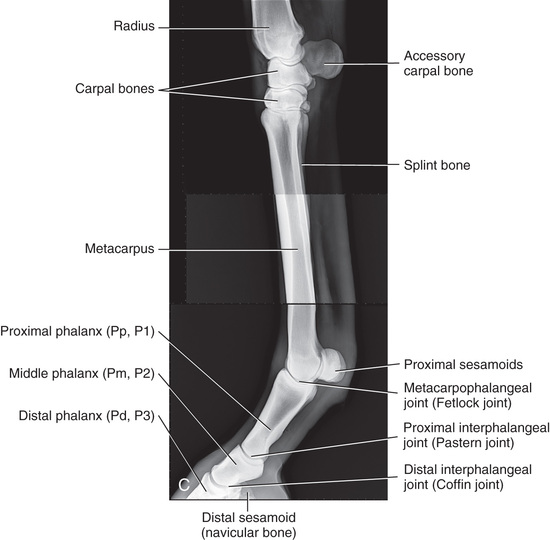

Compare the large-animal anatomy with human and small-animal anatomy (Fig. 24.1). The technical terms are similar but common terms differ.